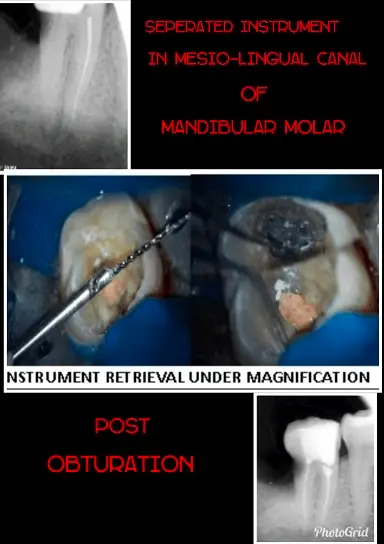

Retrieval of Separated Instruments from the Root CanalUnder Dom

Patient presented with severe pain in lower mandibular molar area. Past dental history indicated attempted root canal treatment 2 weeks back. Radiograph revealed instrument separation in distal canal of mandibular molar. With expertise the instrument was retrieved under Dental Operating Microscope. Root canal treatment was completed successfully and the patient bid off smiling with no pain.